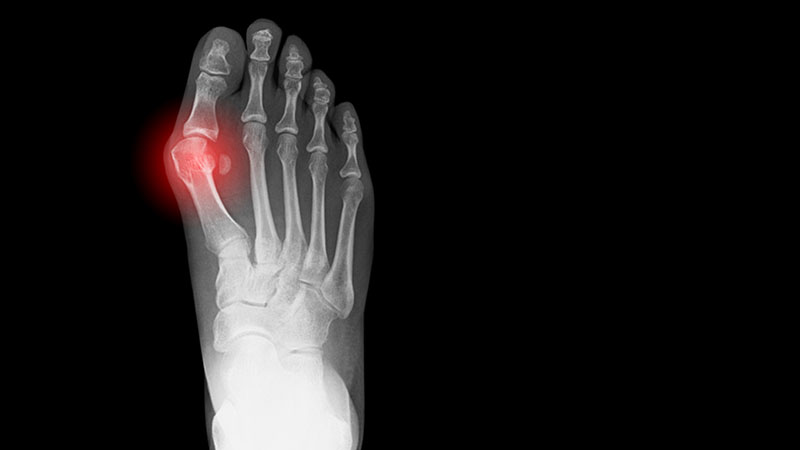

X-ray showing a bunion on a human foot.

• What is a bunion? A bunion (also called hallux valgus) is a bony bump at the base of the big toe that changes the shape of the foot. The misalignment of the big toe joint can cause the big toe to lean toward the second toe, creating the bump.